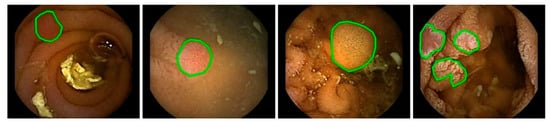

There are various challenges in the automated detection of polyps. As shown in Figure 1 and Figure 2, polyps appear in different sizes, shapes, textures, and color. Their endoscopic appearance can be similar to protruded lesions, flat elevated lesions, and flat lesions. The images even have noisy background with bleeding and endoluminal folds, which suppresses the accuracy of the detection process.

Figure 1.

Images with ground truth polyps (marked in green) from colonoscopy videos.